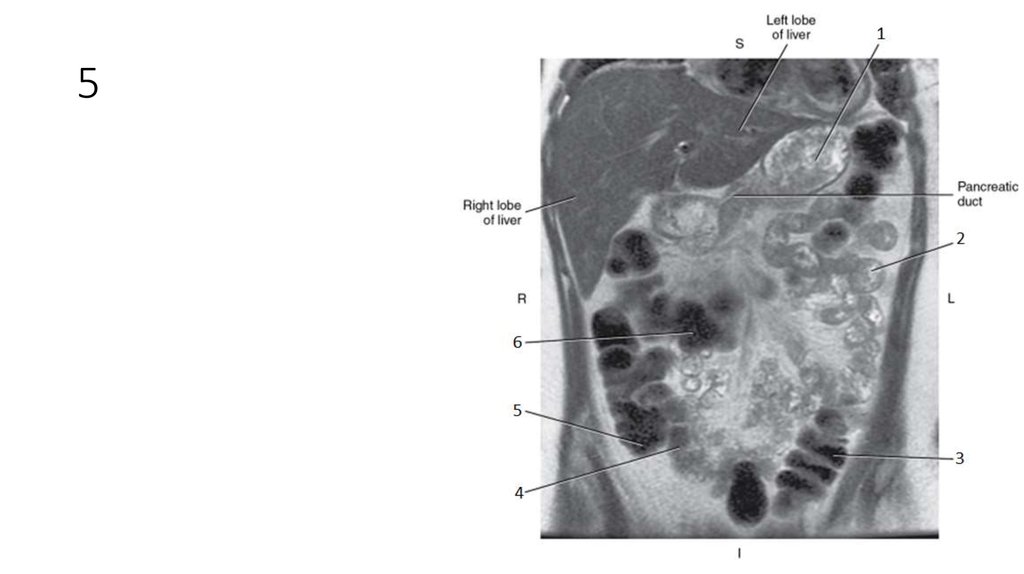

50. 1

51. 1

• Stomach

52. 2

53. 2

• Jejunum

54. 3

55. 3

• Descending Colon

56. 4

57. 4

• Ileum

58. 5

59. 5

• Cecum

60. 6

61. 6

• Transverse Colon